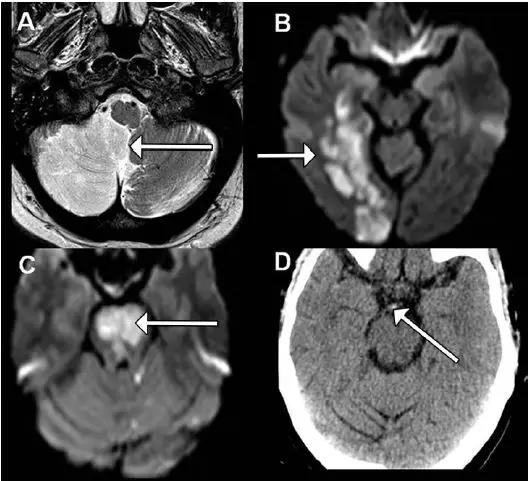

图 2.

颅内椎动脉梗塞中最常见的临床综合征,是由于供应延髓背外侧的血管分支梗塞所致,经常被漏诊或误诊(图 3);

小脑下后动脉梗塞常导致共济失调,其供应部位受损引起的各项局灶性神经功能障碍(图 2)后既发引起同侧后枕部、颈部疼痛;

图 3. 左侧脊髓梗塞。A.MRI T2 扫描成像。B.MRI DWI 扫描成像。

临床特征为同侧同向偏盲、感觉缺失,而无肢体瘫痪(图 2B);基底动脉尖闭塞可导致中脑、丘脑、和部分颞叶、枕叶(大脑后动脉分支供应的部分)的梗塞;脑干被盖区梗塞主要会影响警觉、行为、记忆、动眼和瞳孔等功能。